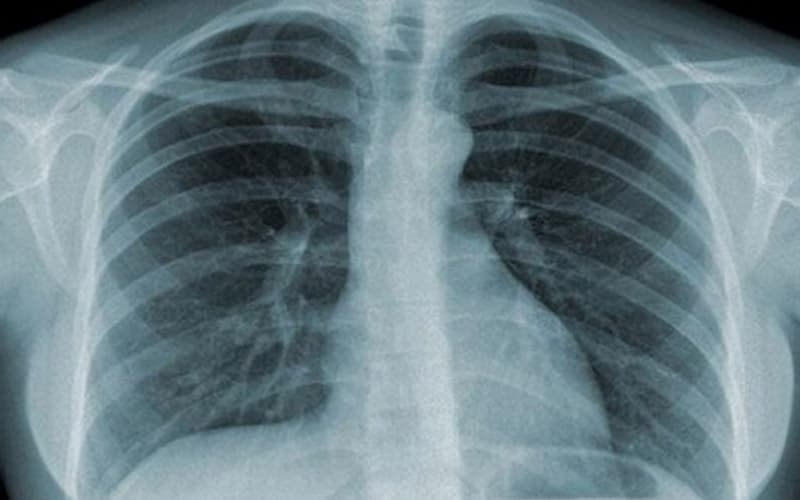

- X-quang ngực thẳng: Phương pháp cơ bản để phát hiện tổn thương nhu mô phổi, khối u hoặc dịch màng phổi.